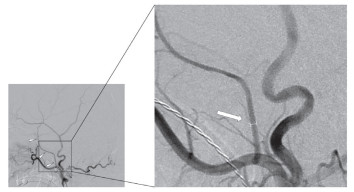

将所有DSA正侧位图像传输到影像工作站进行分析(图 1)。(1)测量段选择:由于MMA主干颅内段血管走行相对平直,能够减少因血管弯曲干扰导致的测量误差,所以选择该段。(2)测量时机:在动脉中期,当造影剂充分充盈且血流稳定时进行测量,此时血管显影清晰,运动伪影较少。(3)测量方式:由2名神经外科医师采用盲法分别测量双侧MMA直径(单位:mm),取2人测量平均值进行统计分析;若测量差值>0.2 mm,由第3位高年资医师复核,经讨论达成一致意见。

图  1  基于DSA图像测量CSDH患者的MMA直径

Fig.  1  Measurement of MMA diameter in CSDH patients based on DSA images

The long triangles indicate the MMA, the arrow indicated the measurement site, and the line segment represents the measured MMA diameter. DSA: Digital subtraction angiography; CSDH: Chronic subdural hematoma; MMA: Middle meningeal artery.